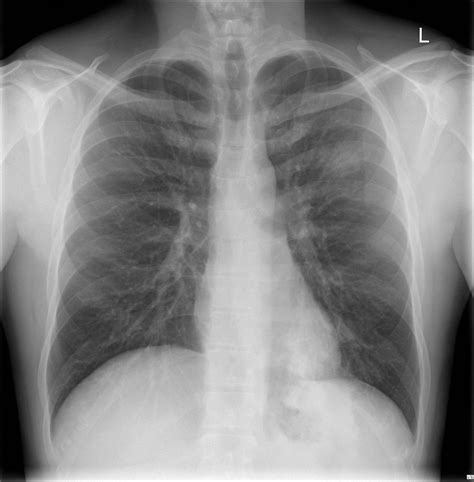

When a radiologist reviews a Pneumonia X-ray, they are looking for specific indicators of disease. Healthy lungs on an X-ray typically appear black because they are filled with air, which does not block the X-ray beams. Conversely, infected tissue blocks these beams, leading to white areas on the film. These findings are often referred to in clinical reports as "infiltrates" or "consolidation."

Clear black lung fields Healthy, air-filled lungs

While a Pneumonia X-ray is the "gold standard" for initial diagnosis, it is not infallible. In some early stages of the disease, the X-ray might appear normal even if the patient is symptomatic. This is common in cases of "walking pneumonia" or very mild infections. If your clinical symptoms are severe but your X-ray is clear, your doctor may suggest further tests, such as a CT scan, blood work, or a pulse oximetry test to measure oxygen levels.

Furthermore, an X-ray can confirm the presence of pneumonia but does not always tell the doctor the specific cause—whether it is viral, bacterial, or fungal. This is why physicians often combine imaging results with physical examinations, listen to your lungs with a stethoscope, and consider your medical history before prescribing antibiotics or other treatments.